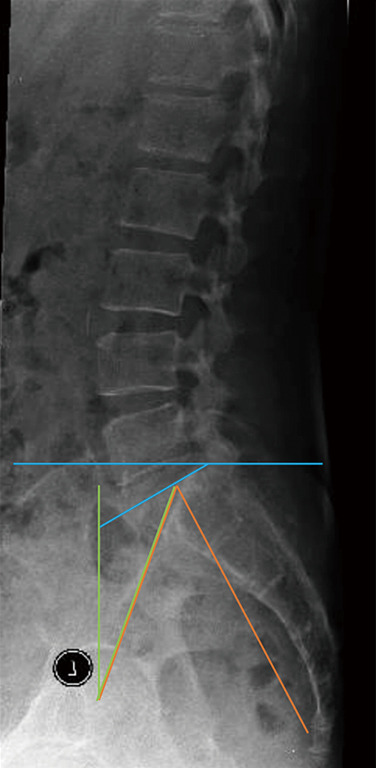

背景:与单纯减压术(DA)相比,使用层间器械作为减压术的辅助手段来治疗症状性腰椎管狭窄症(LSS)的放射学结果方面的文献十分有限。本研究旨在评估和比较脊柱减压术和带 ILD 的减压术(D+ILD)的 5 年放射学疗效:我们对前瞻性收集的数据进行了回顾性分析,这些数据来自 2007-2015 年间接受脊柱减压术并植入或未植入 ILD 的 94 例患者。符合研究标准的无症状 LSS 患者可接受脊柱减压术,无论是否植入 ILD。接受ILD植入的患者被归入D+ILD组(39人);而选择DA的患者被归入DA组(55人)。对术前、术后即刻、术后 2 年和 5 年的放射学指标进行评估:结果:共有 94 名患者,DA 组 55 人,D+ILD 组 39 人。两组患者的矢状平衡参数,即平均骨盆入径、骨盆倾斜、骶骨斜度和骨盆入径减去腰椎前凸(PI - LL)在术后 5 年的随访中均无明显变化。两组间的矢状平衡参数无显著差异。DA组与D+ILD组相比,整体前凸无明显差异,但D+ILD组的矢状角(指数水平)比DA组明显减少了2.3°(P=0.01)。在对照组中,术后椎间盘前部、椎间盘后部和椎间孔高度无明显差异。与对照组相比,D+ILD组的前椎间盘高度、后椎间盘高度和椎间孔高度平均分别增加了1.3毫米、1.8毫米和4.7毫米。两组患者的所有临床结果均有明显改善,即 36 项简表调查身体部分摘要(SF36 PCS)、36 项简表调查精神部分摘要(SF36 MCS)和视觉模拟量表(VAS)。比较两组患者,D+ILD 组的 SF36 MCS 有明显改善(P=0.01),但 SF36 PCS 和 VAS 没有差异。再手术率相当:我们的研究发现,在腰椎管狭窄症的治疗中,使用ILD作为辅助设备与DA相比,可显著改善椎间盘前部、椎间盘后部和椎管峡部的高度,预计干预水平的局灶性椎体后凸在5年后不会改变腰椎前凸和矢状平衡。

Results: There were a total of 94 patients with 55 in the DA group and 39 in the D + ILD group. In both groups, there was no significant change post-operatively in the sagittal balance parameters namely, the mean pelvic incidence, pelvic tilt, sacral slope and pelvic incidence minus lumbar lordosis (PI - LL) during the 5-year follow-up. Comparing between the groups, there was no significant difference in sagittal balance parameters. Comparing between DA versus D + ILD, there was no significant difference in overall lordosis, but the D + ILD had a significant reduction in sagittal angle (at the index level) of 2.3° compared to the DA group (P=0.01). In the control group, there was no significant difference in the anterior disc, posterior disc and foraminal height post-operatively. In the D + ILD group, there was a significant mean increase of 1.3 mm in anterior disc height, 1.8 mm in posterior disc height and 4.7 mm in foraminal height compared to the control group. In both groups, there was significant improvement in all clinical outcomes namely 36-item short form survey physical component summary (SF36 PCS), 36-item short form survey mental component summary (SF36 MCS) and visual analogue scale (VAS). Comparing the groups, there was significant improvement in the D + ILD group in SF36 MCS (P=0.01) but no difference in SF36 PCS or VAS. Reoperation rates were equivalent.